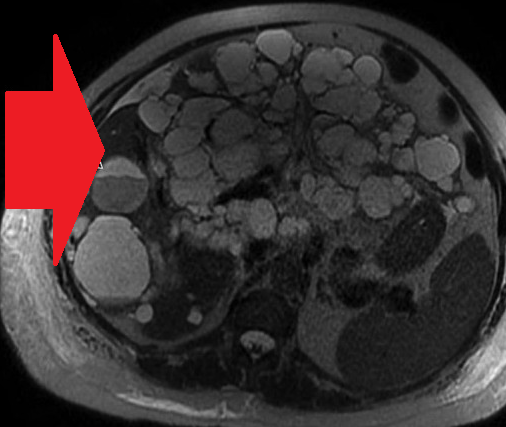

Polycystic liver disease. Red arrow. Infected hepatic cyst (Courtesy Dr. V. Penopoulos)